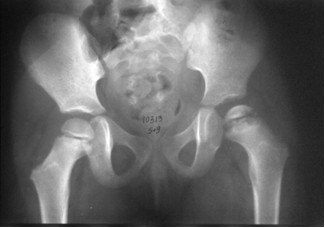

Dziecko w wieku 5 lat i 9 miesięcy zgłosiło się do ortopedy z powodu dolegliwości bólowych lewego stawu kolanowego i okresowych dolegliwości bólowych lewego stawu biodrowego. W badaniu klinicznym stwierdzono niewielkie ograniczenie ruchów odwodzenia w stawie biodrowym i rotacji do wewnątrz. Podczas chodzenia dziecko wyraźnie utyka na kończynę dolną lewą. Objaw Trendelenburga jest dodatni. Wykonany w dniu badania radiogram stawów biodrowych zamieszczony jest poniżej. Obraz kliniczny i radiologiczny przemawia za: